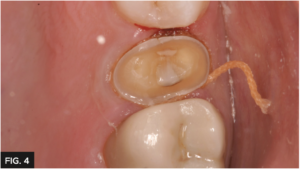

The tooth was prepared for a full coverage crown using a Brasseler #850.016. Gingival retraction was carefully achieved using a double cord technique placing 2 layers of Ultradent’s #000 UltrapakTM retraction cord. (FIG. 4)